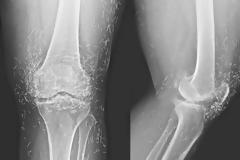

Μια 65χρονη γυναίκα από τη Νότια Κορέα υπέφερε από αρθρίτιδα και πήγε να κάνει μια σειρά ακτινογραφιών, στα πλαίσια παρακολούθησης της ασθένειάς της